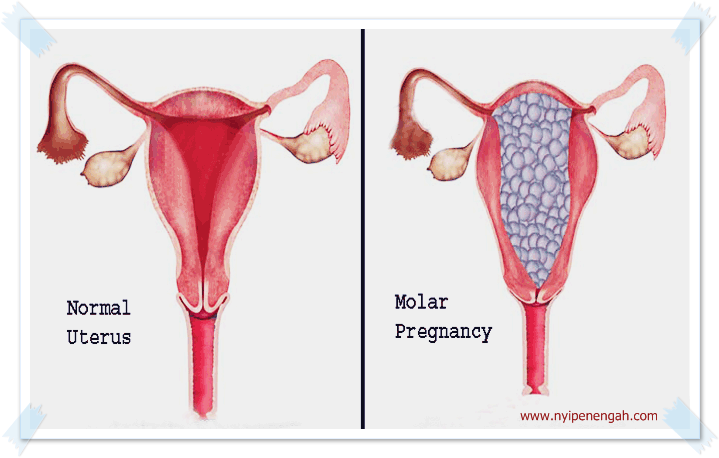

Waspada Hamil Anggur Atau Hamil Kosong Nyi Penengah Dewanti

Waspada Hamil Anggur Atau Hamil Kosong Nyi Penengah Dewanti